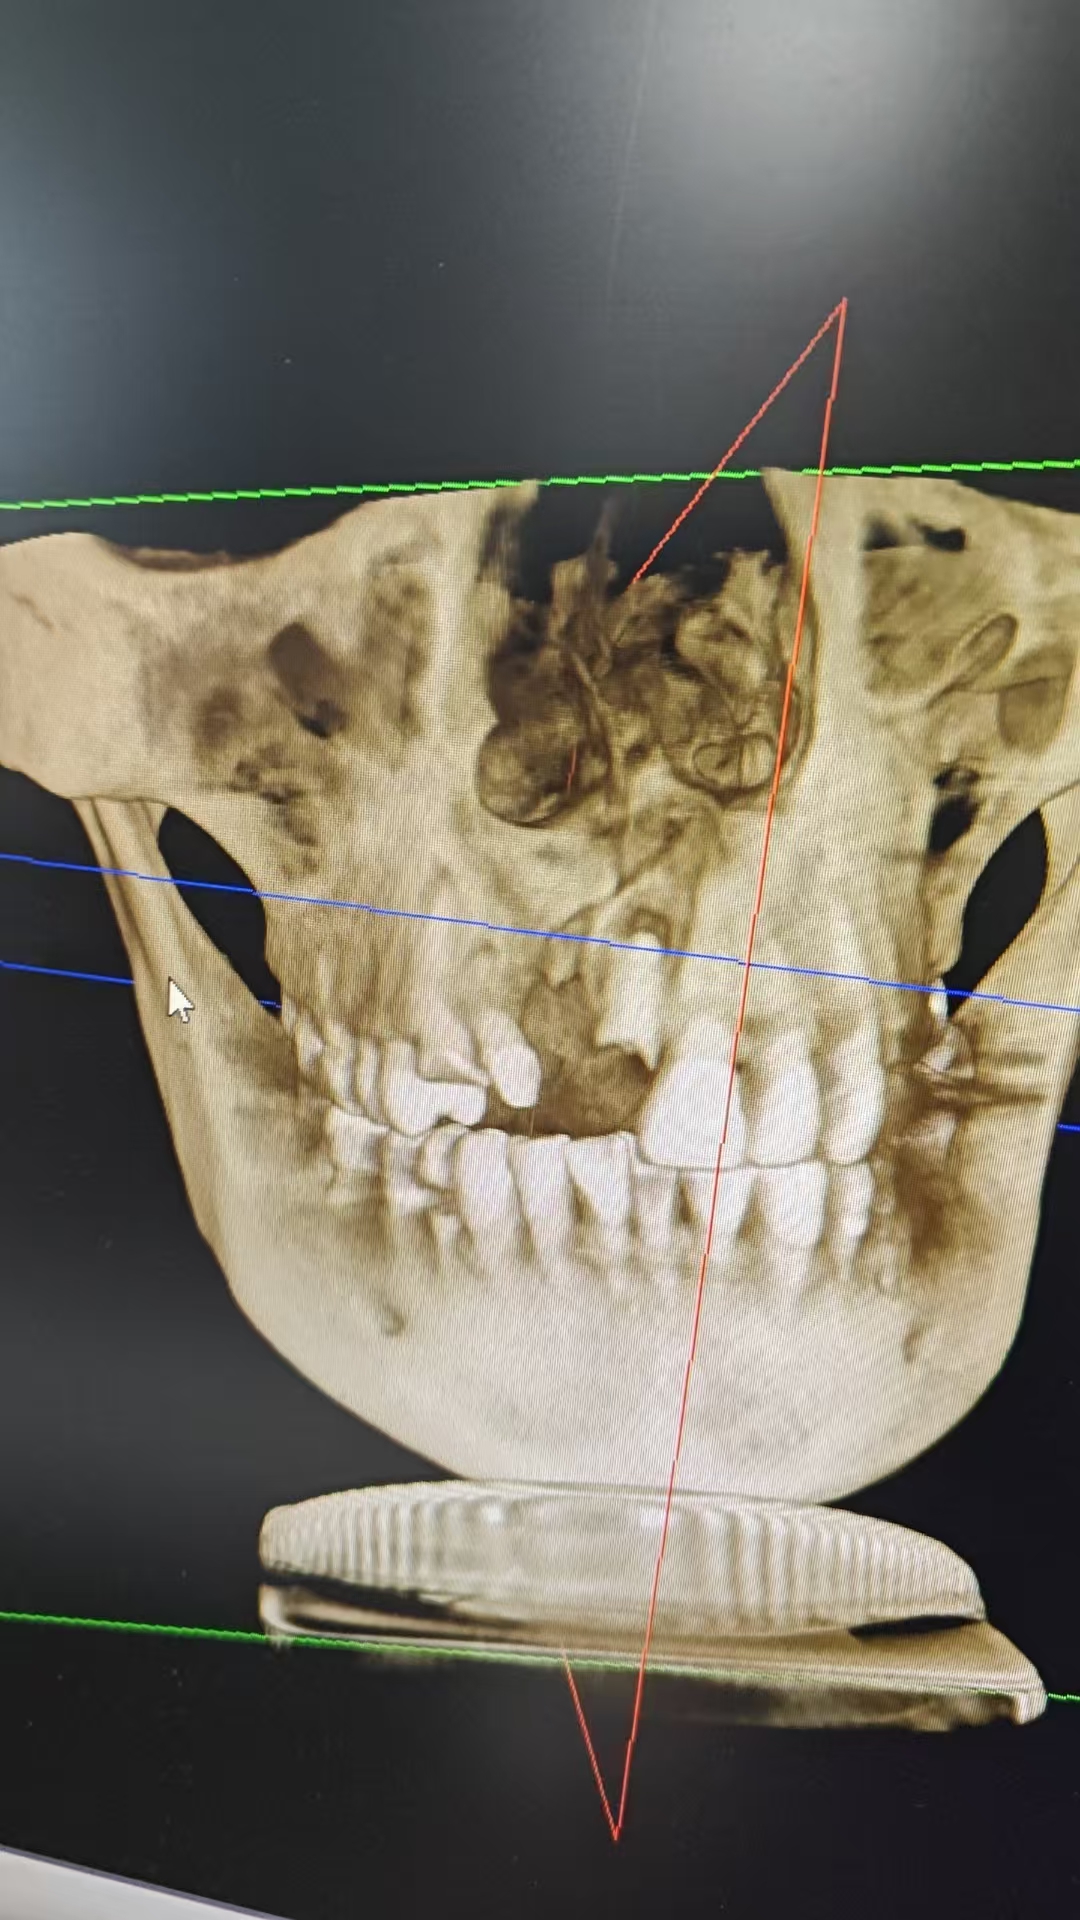

CBCT(锥形束 CT,看种植牙、复杂阻生智齿等):辐射量相对更高,但也分 “小视野” 和 “大视野”。小视野 CBCT(只拍局部)大约 84μSv,相当于做一次胸部 X 光(约 100μSv);大视野 CBCT(拍全颌骨)大约 212μSv,相当于 10 天的自然本底辐射(我们每天呼吸、晒太阳,自然环境中的辐射大约 20μSv / 天)。

划重点:我们每年从自然环境中接受的 “本底辐射” 大约有 2000-3000μSv。也就是说,即使拍一次大视野 CBCT,辐射量也只占全年自然辐射的 7% 左右!

只有 “必须用 X 线辅助诊断” 时才会开检查。比如蛀牙太深到牙神经、智齿位置复杂可能伤邻牙、种植牙需要精确测量骨量 —— 这些情况,X 线能帮医生看得更清楚,避免误诊漏诊。

现在的数字化牙片(取代传统胶片)通过缩短曝光时间,辐射量比 20 年前降低了 50% 以上;CBCT 也有 “小视野模式”,只拍需要的部位,减少不必要的辐射。